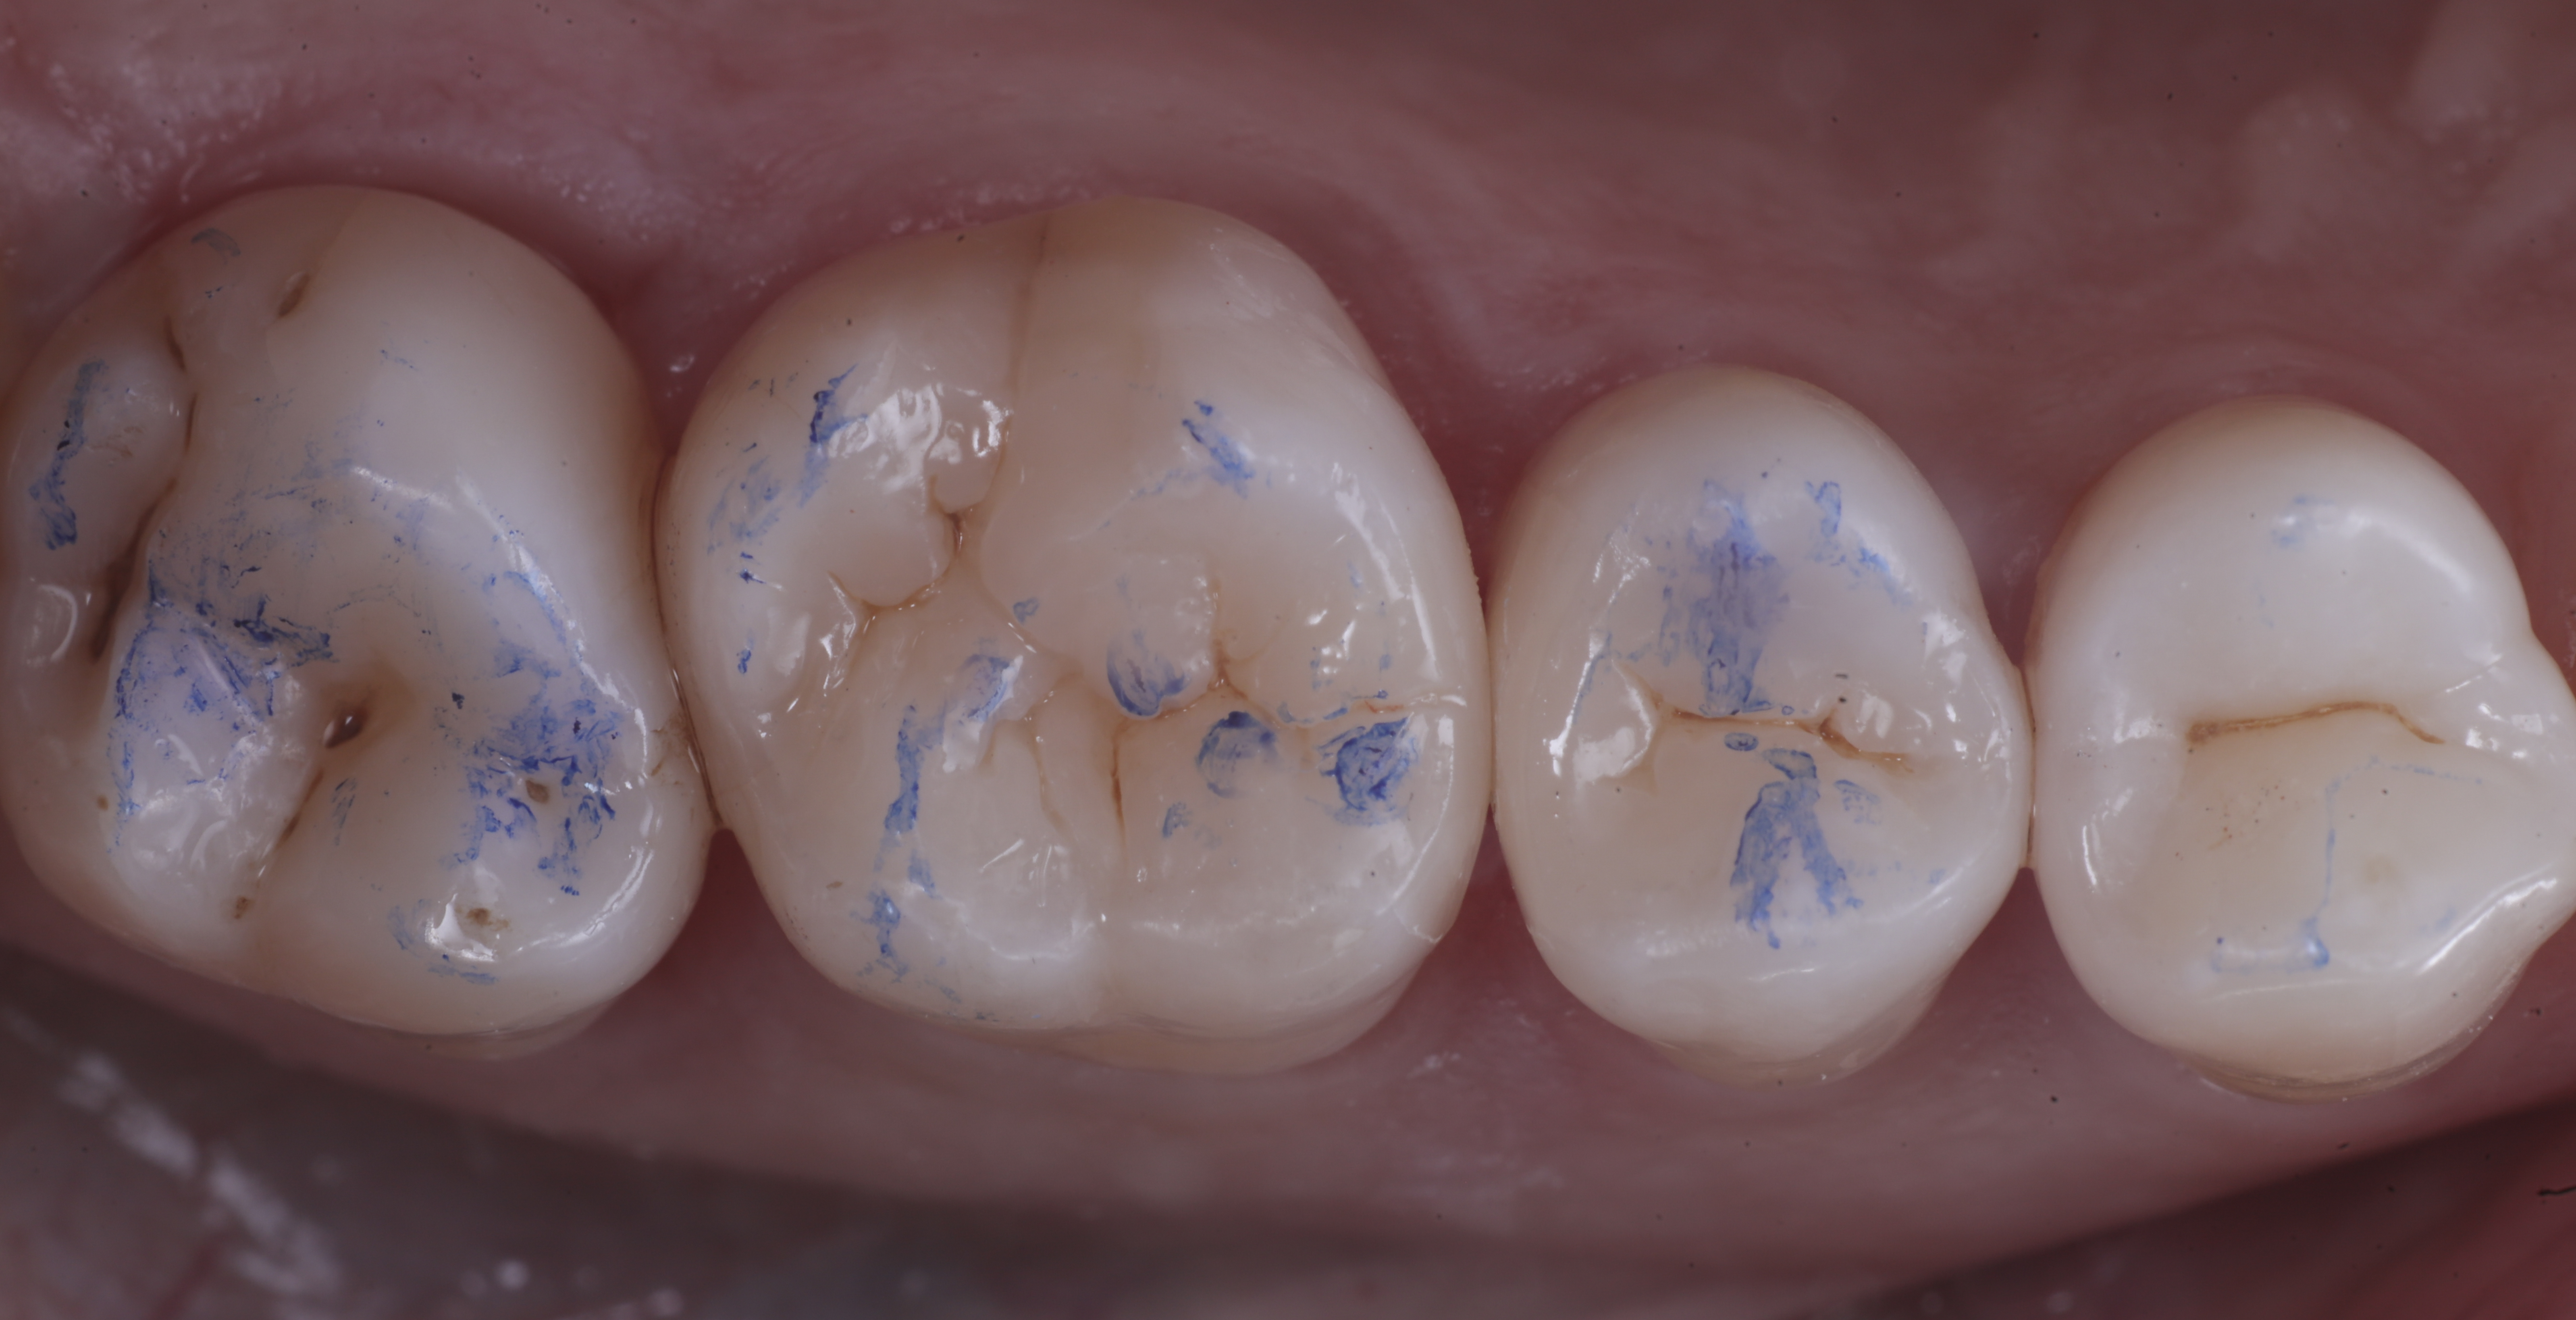

foto 9 Modellazione ed aspetto vestibolare

foto 10 Modellazione ed aspetto palatino

foto 11 Restauri ultimati sotto controllo occlusale